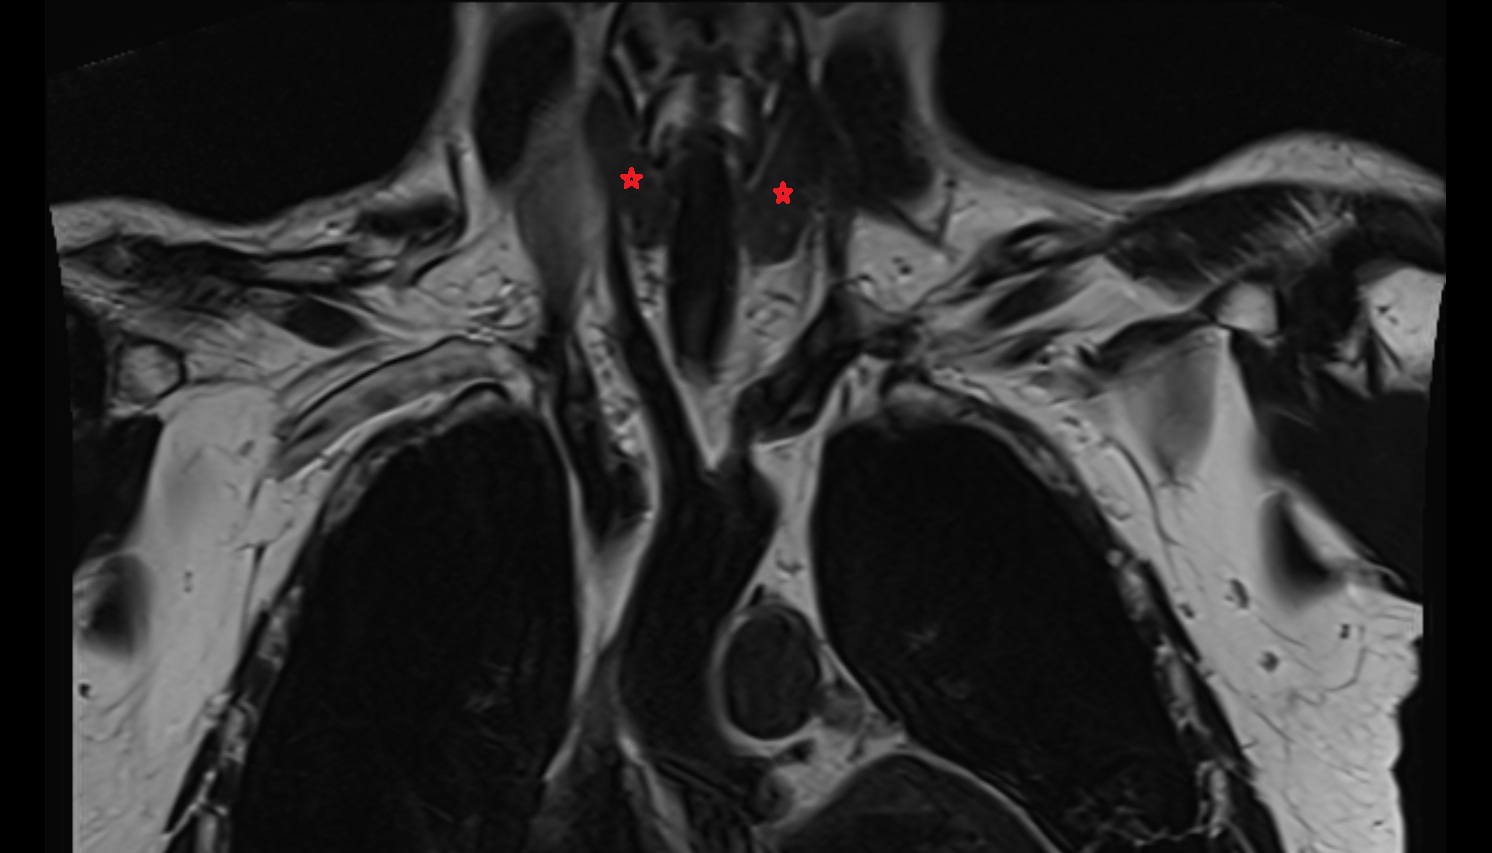

- Lateral atlantoaxial joint

- Atlantooccipital joint